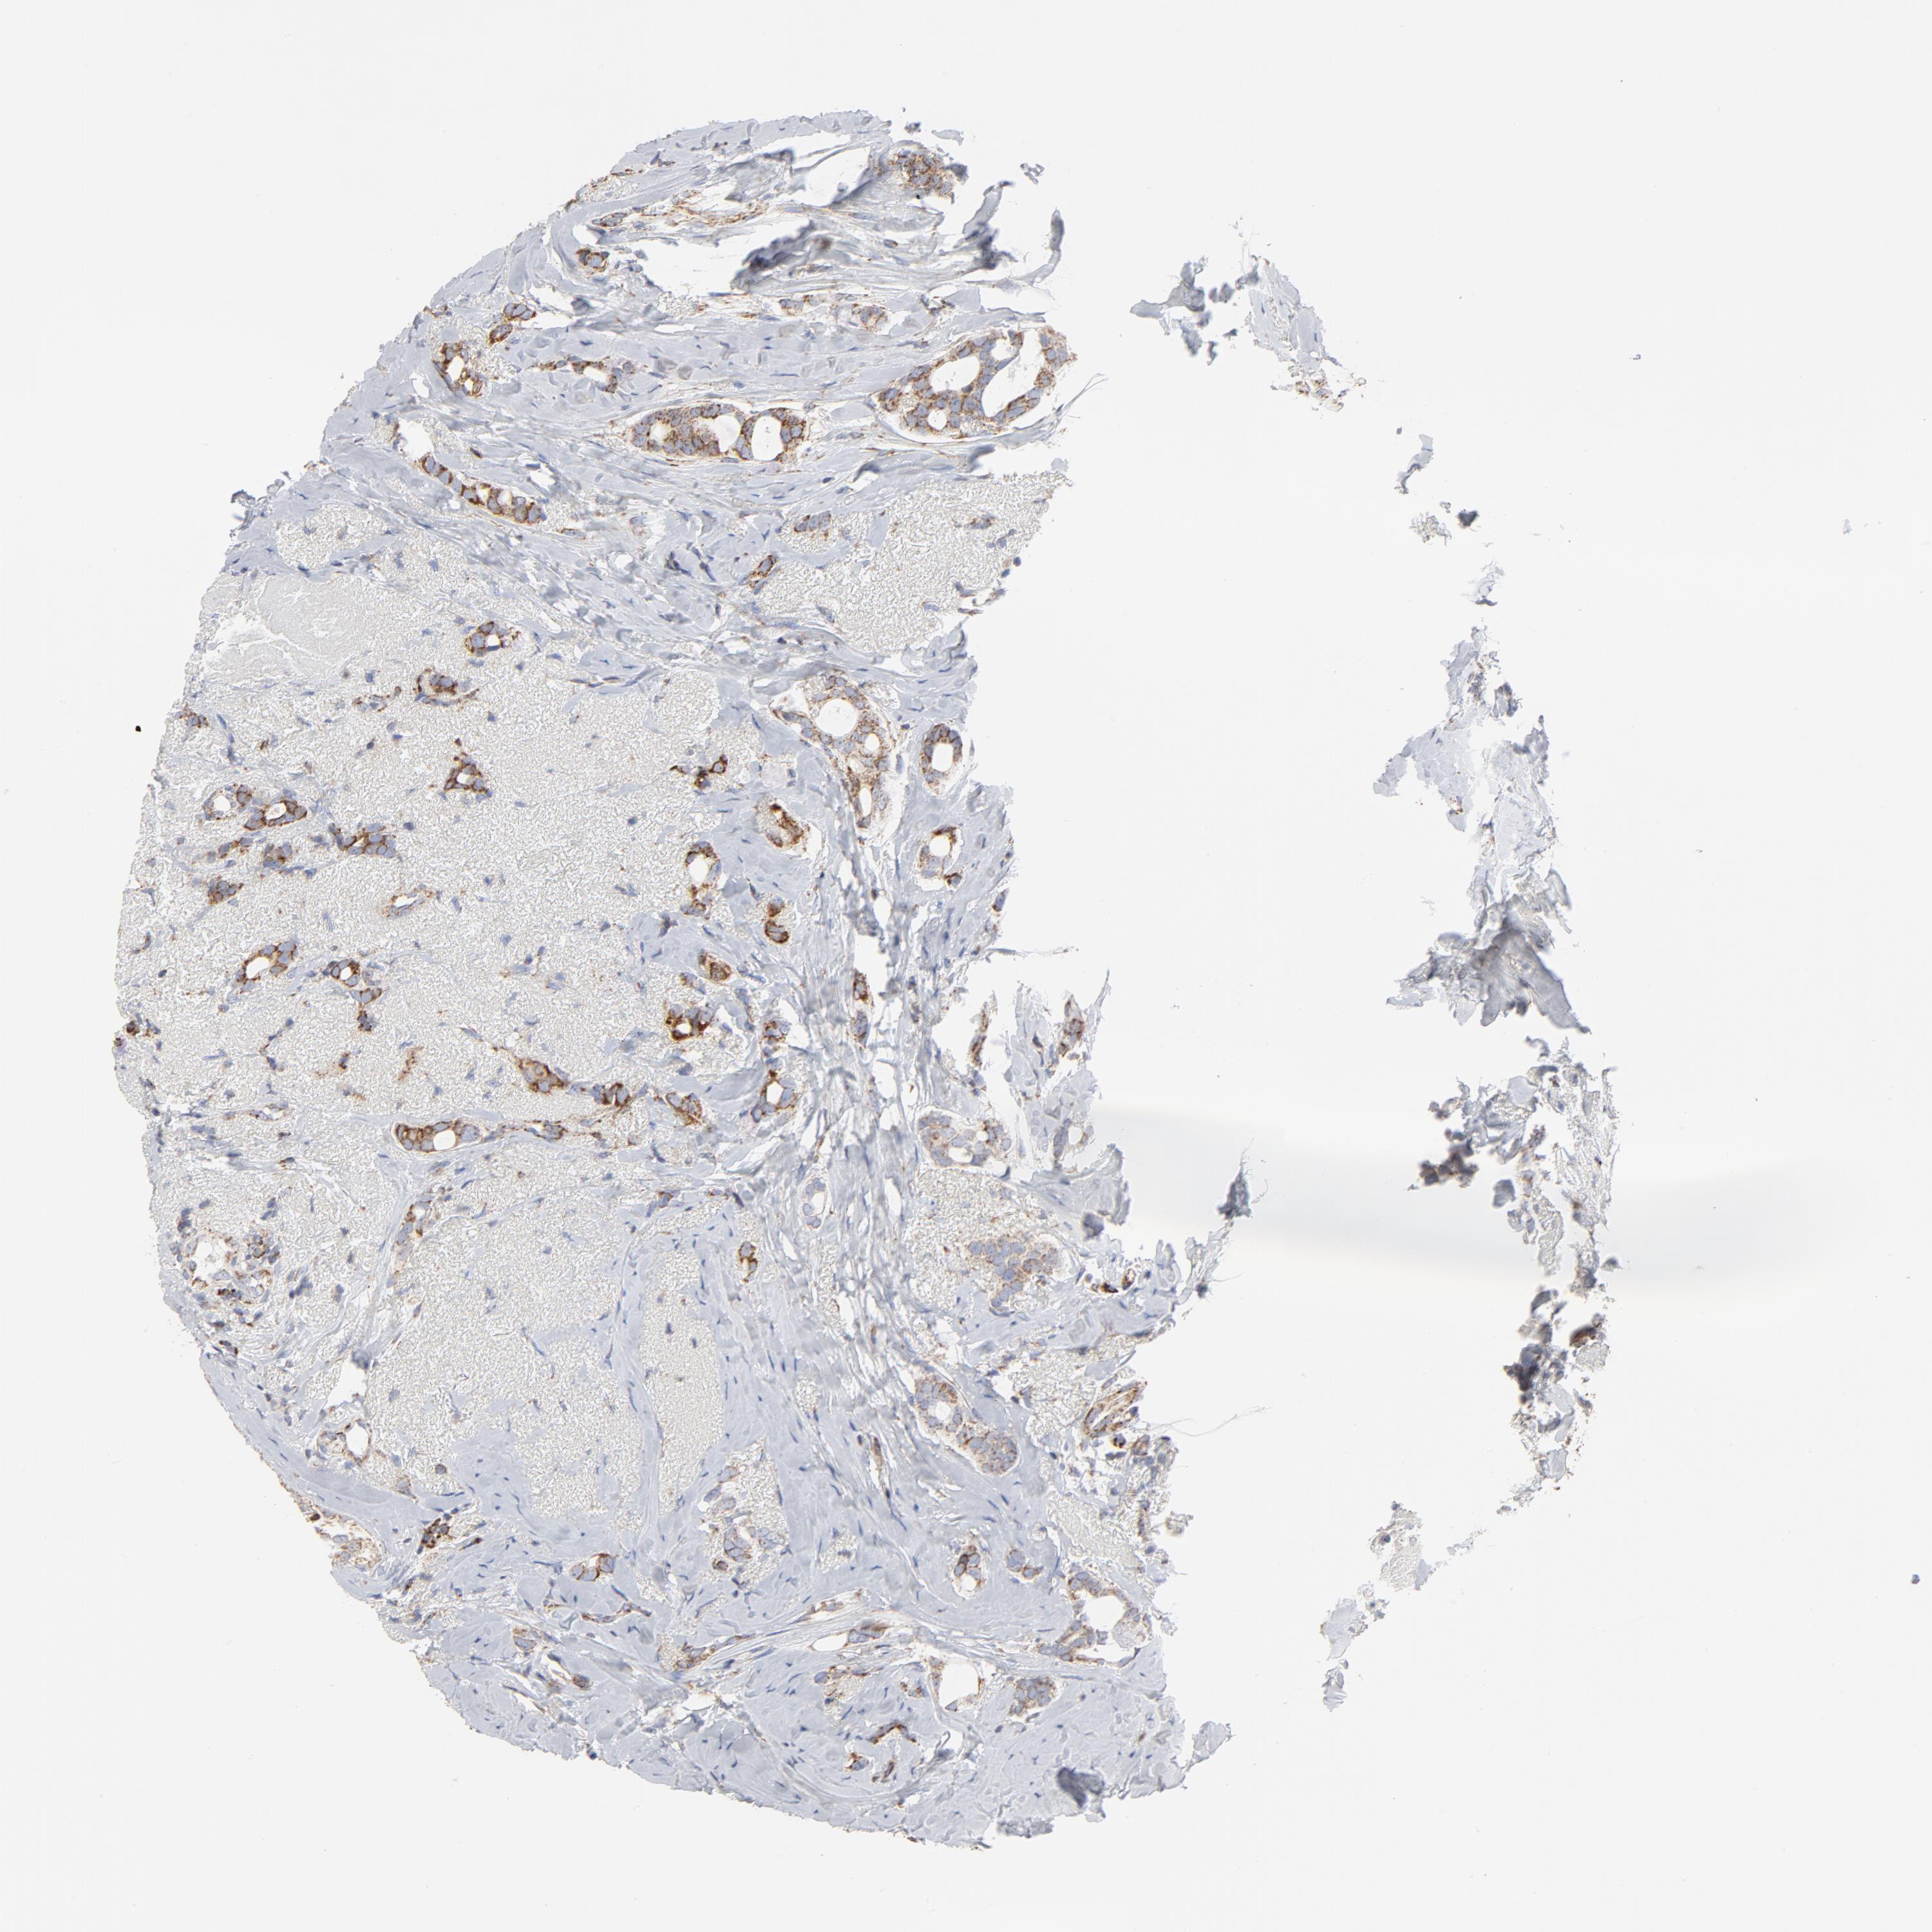

BRCA TCGA BRCA VALIDATION PROTEIN EXPRESSION